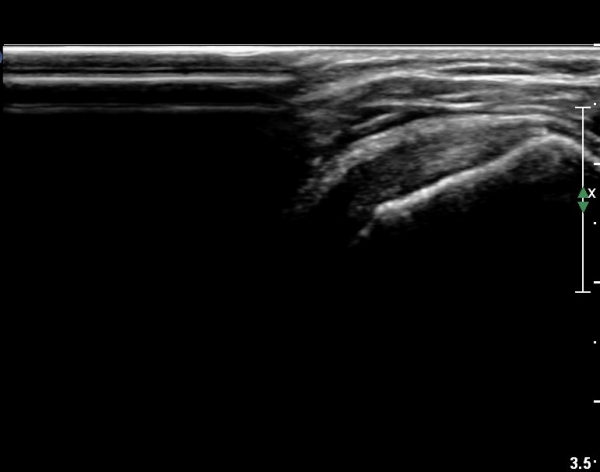

°ß°©ÇÏ±Ù°Ç ÇϺΠÁ¾´Ü¸é°Ë»ç¿¡¼­ °ß°©Çϱٰdz»  ÀÛÀº ¼®È¸È­ µ¢¾î¸®°¡ °üÂûµÈ´Ù(»çÁø 3, 4).